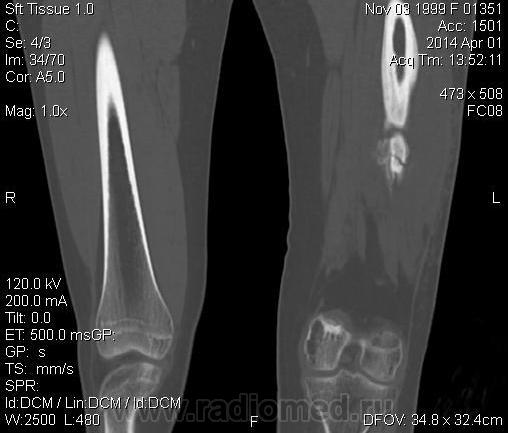

Молодая дама (14 лет) с переломом срдней трети диафиза левого бедра в анамнезе (декабрь 2012 г). Ломала ногу несколько раз в этом месте. Сейчас состояние после МОС. Как следует понимать изменения в кости, формируется ли ложный сустав?

Похоже ложный сустав сформировался. Но при нём обычно большие напластования костной мозоли, здесь их нет. В таких случаях смотрю при скопии подвижность.

Ох, не хочется думать о ложном суставе в 14 лет... По срокам под ложный сустав подходит, он характеризуется замыканием костномозгового канала с формированием подобий суставных поверхностей. У нее же есть хиленькая периостальная костная мозоль по задней поверхности бедра удерживающая отломки в правильном положении. Я склонна думать, что это скорее застарелый перелом (оно же замедленная консолидация). Здесь очень важно посмотреть предыдущие снимки (поиск рефрактуры, либо отсутствия полной консолидации).

При выраженной костной мозоли между отломками ложный сустав формироваться не может в принципе.

Настоящего, родного ложного сустава пока нет, хотя костномозговой канал дистального отломка уже закрыт - образовалась склерозированная замыкательная пластина. Варусная деформация почти в 165 градусов... Я бы заключилась неполной консолидацией и варусной деформацией, прогностически формирование ложного сустава очень вероятно.